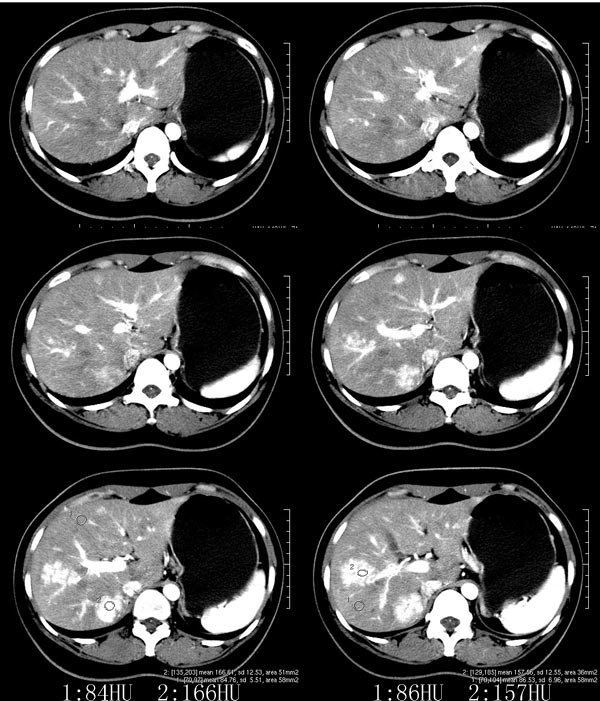

以下是引用52yingxiang在2007-9-16 10:16:00的发言:[br]肝脏局灶性结节增生影象表现(fnh)[br][br]肝脏局灶性结节增生是一种少见的肝脏良性肿瘤,可表现为边界清楚并无包膜的实质性肿块。病变大小不一,多系单发,亦可多发。组织学上是由结构紊乱的肝细胞、库普弗细胞、胆管、血管和粗厚的纤维性间隔所组成。[br]局灶性结节增生的ct表现可归纳为6点:[br]1、密度变化是其特征性改变,平扫多为低密度,少数为等密度,无论增强的早期或晚期均可能呈等密度,增强扫描有助于发现平扫为等密度的病灶;[br]2、中心疤痕,部分病灶在动态ct扫描时早期可看到中心疤痕增生性结节性病灶,ct血管造影也可看到普通ct不能显示的车轮状血管和车轴样改变;[br]3、纤维性分隔影,平扫为低密度,增强后为高密度;[br]4、包膜征象,增强后可以出现包膜强化,晚期较明显;[br]5、邻近血管的改变,主要是肝静脉受压,是发现等密度病变的重要依据;[br]6、瘤内胆管显影,这需要在胆管造影增强的情况下方能显示,出现率不高。[br][br]本例特点: 平扫低密度,增强动脉期明显强化,中心点条状低密度影(考虑纤维瘢痕),静脉期及延时期明显退减并与肝呈等密度,但中心仍可见低密度灶。[br]考虑肝脏局灶性结节增生(fnh)